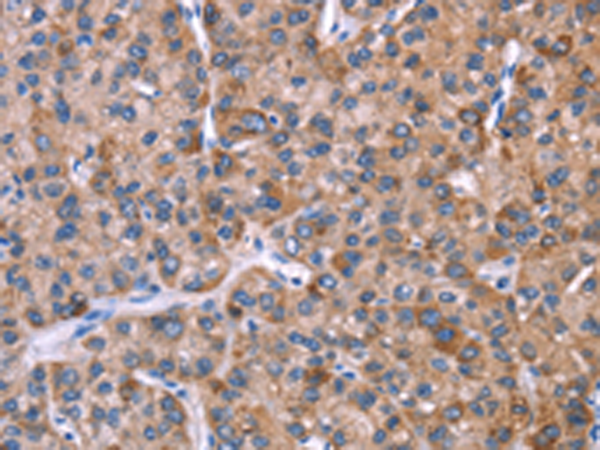

分类: 科研抗体货号: P04914别名: H963应用: WB,IHC反应种属: Human